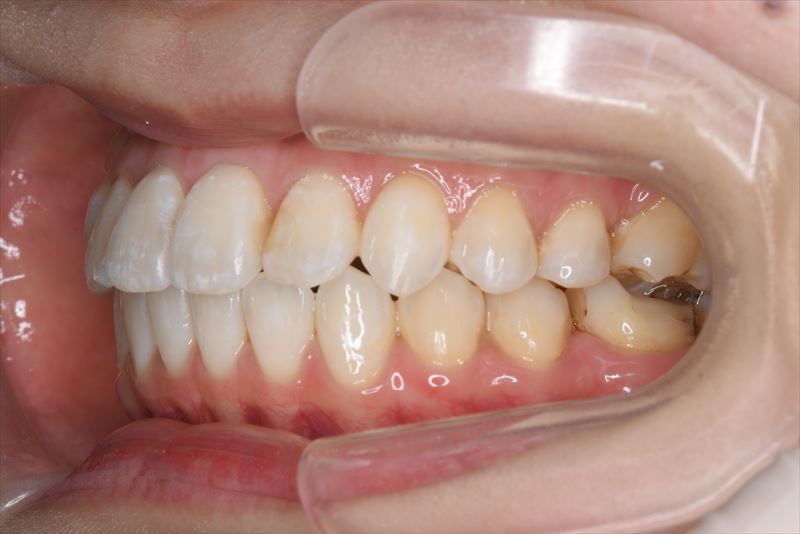

治療前

- 両側2番クロスバイト、叢生、上顎左側6番根尖病巣

- 上顎左側6番抜歯